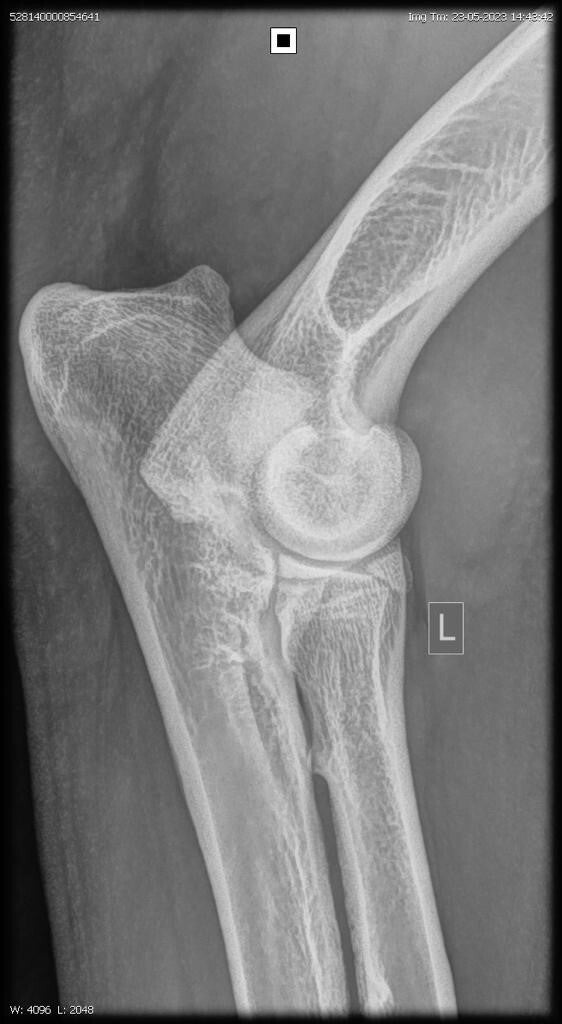

23/06/2023: Röntgenopname ellenbogen + heupen -> geen afwijkingen (heupdysplasie A, ED vrij)